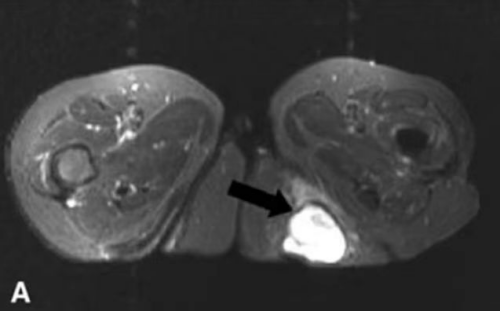

图中箭头所指为“坐骨结节囊肿”